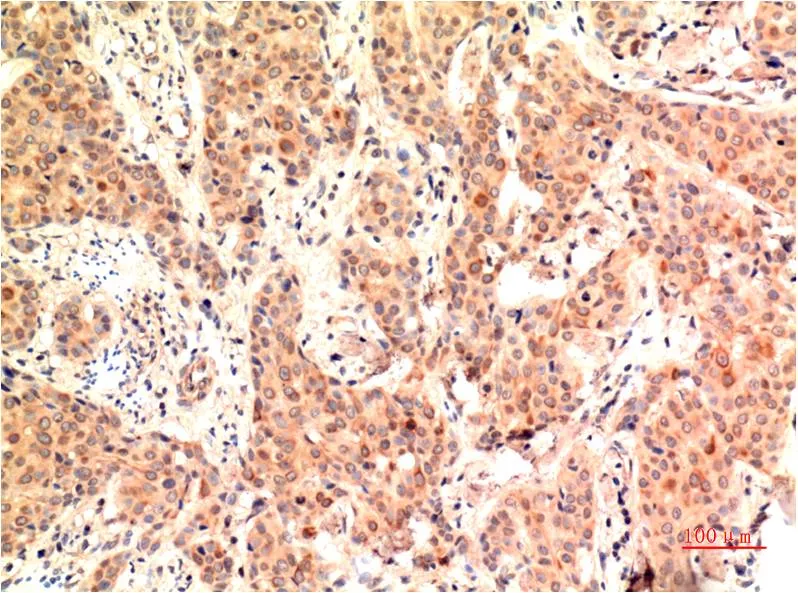

IKB beta (5H3) Mouse Monoclonal Antibody

Cat: AMM00735

Application:IHC-P

Reactivity:Human,Rat,Mouse

Conjugate:Unconjugated

Gene Name:NFKBIB